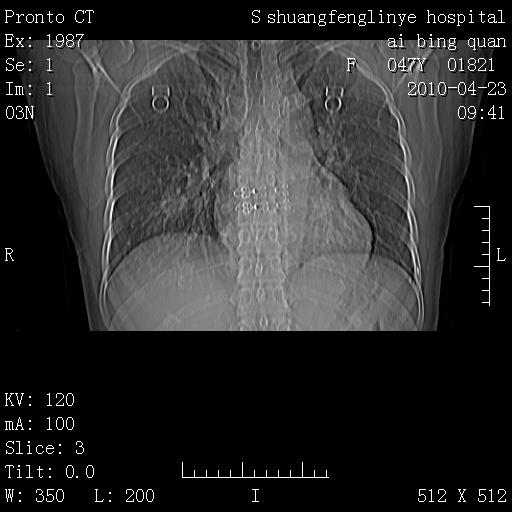

标题: CT25944:胸痛、气短、前几日高烧!肺Ca?请会诊! [打印本页]

标题: CT25944:胸痛、气短、前几日高烧!肺Ca?请会诊!

kaolv 周围型肺癌并同肺转移

双肺多发结节,考虑转移瘤,肺癌肺转移不除外

周围型肺癌并肺转移

双肺多发结节,部分密度较高,最大结节边缘光滑。临床有“胸痛、气短、前几日高烧”病史。首选考虑:右肺感染性病变!建议积极消炎后复查!